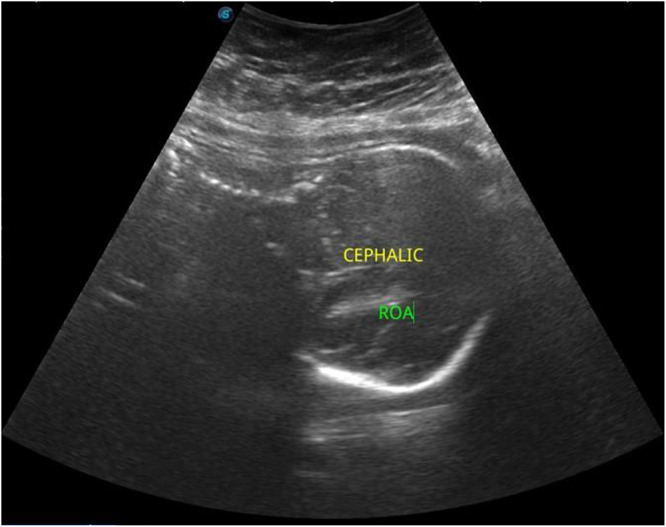

Case presentation: We report the case of a 30-year-old woman at 33 weeks of gestation who presented with right lower quadrant pain initially misattributed to round ligament strain. Her condition deteriorated over several days with worsening abdominal pain, fever, and leukocytosis. Imaging confirmed an acute uncomplicated appendicitis. After multidisciplinary evaluation and counseling, the patient declined surgery due to concerns over fetal safety. A conservative approach with intravenous antibiotics was initiated, resulting in complete clinical resolution. The patient delivered a healthy infant at term, without complications or recurrence.